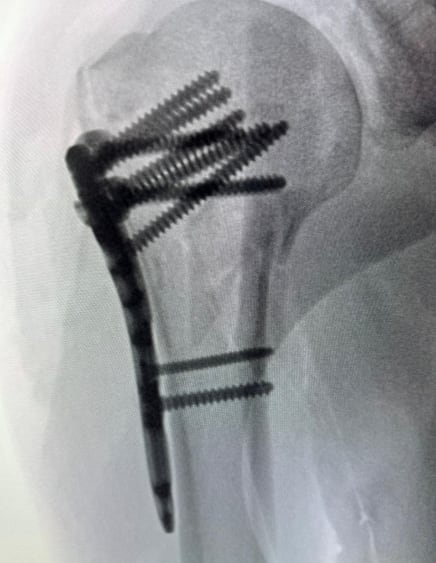

Director de programa deportivo sufre accidente en bicicleta y tienen que reconstruirle el hombro

El comunicador es un apasionado del ciclismo y salió a rodar el primer día del 2026

Cortesía Bernal Arce

Bernal Arce Salas tiene 12 años de estar al frente del programa Meridiano Deportivo, el cual le da cobertura al Club Sport Herediano. (La Nación/Cortesía Bernal Arce)